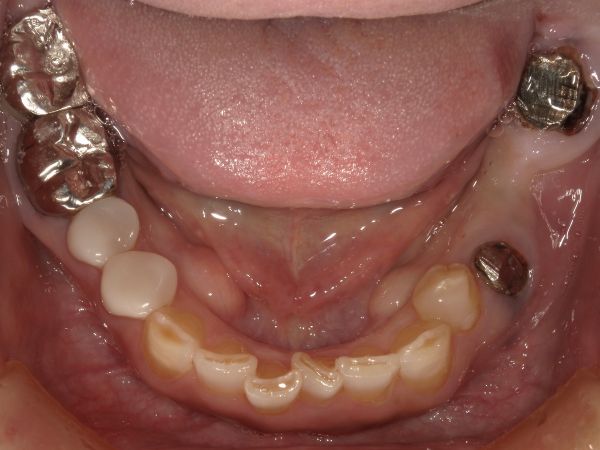

こちらが初診時のお口の中の状態です。

左下5番目と7番目を土台としたブリッジが外れてしまった状態です。

メタルコアという金属の大きな土台がお口の中に剥き出しとなっているのが分かります。